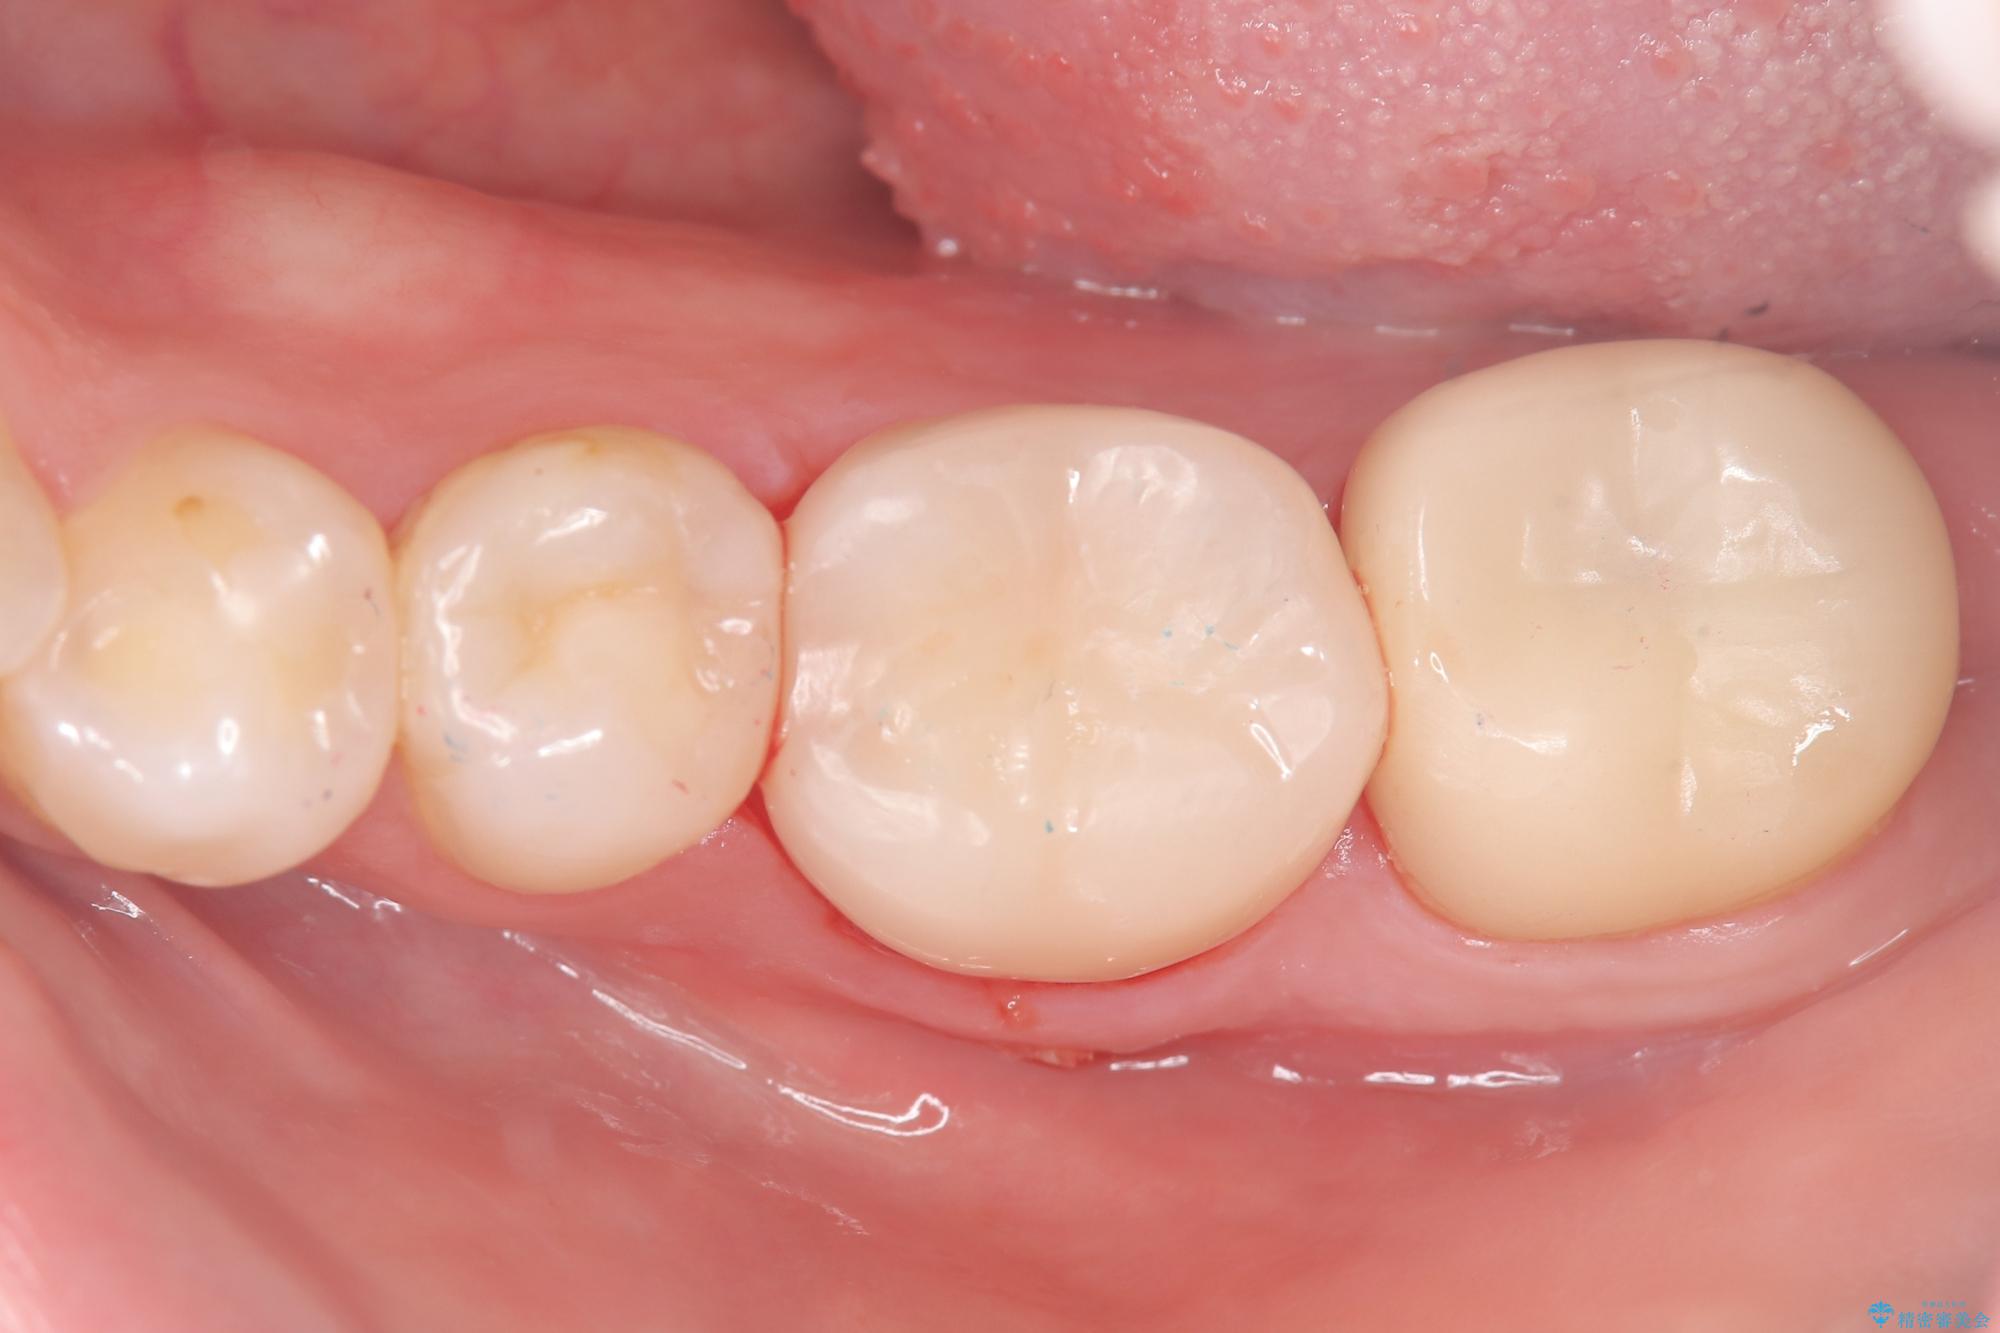

保存が難しい左下6番目の歯を抜歯し、左下8番目の歯(親知らず)を抜歯窩に移植しました。歯牙移植後の動揺防止のため暫間固定を行っています。

骨との定着を確認し、今後矯正治療を行う予定のためレジン冠をセットしています。